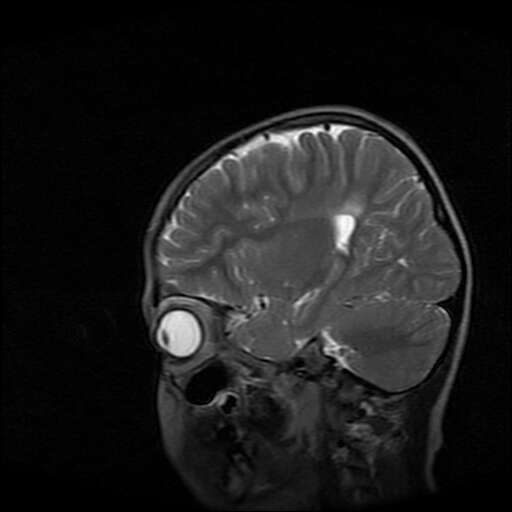

女,7岁,三岁才说话、走路。现智力尚可,走路不稳。临床怀疑大脑发育不全。

考虑 脑白质发育不良

脑折质变薄,双侧侧脑室稍扩张,支持考虑脑折质发育不良

侧脑室周围白质软化症。

考虑胼胝体发育不全,髓鞘形成不良。

支持考虑胼胝体发育不全,髓鞘形成不良。

脑裂畸形伴灰质异位

侧脑室周围白质数量减少,侧脑室不对称性扩大,左侧侧脑室后角呈方形改变,脑沟加深,结合临床考虑脑室周围白质软化症(pvl)。期待结果!

只看出灰质异位

支持脑白质发育不良。